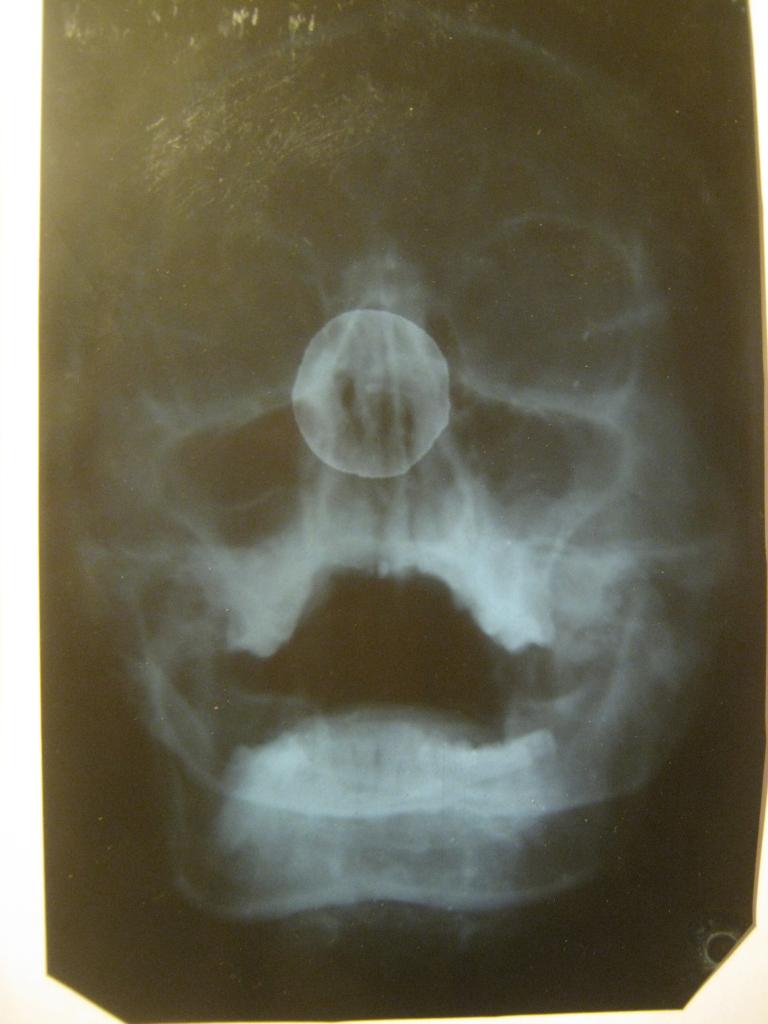

вот эта часть снимка

надо пойти к доктору - верхняя 7 с очень большой пломбой - может в этом зубе проблема.... и свежий снимок для сравнения - как там мудрый - может и продвинулся...

Снимок достаточно свежий, месяц назад делала, а болит давно, при простукивании, нажатии и т.п. ни один зуб не реагирует.

Скорее всего причина в 8-м зубе в.ч.

И все таки скорее всего проблема в суставе.

а что сказать?! ржачные! (только не обижайтесь).

о чём речь? о какой "кисточке"???

информативность таких снимков по зубам = 0.